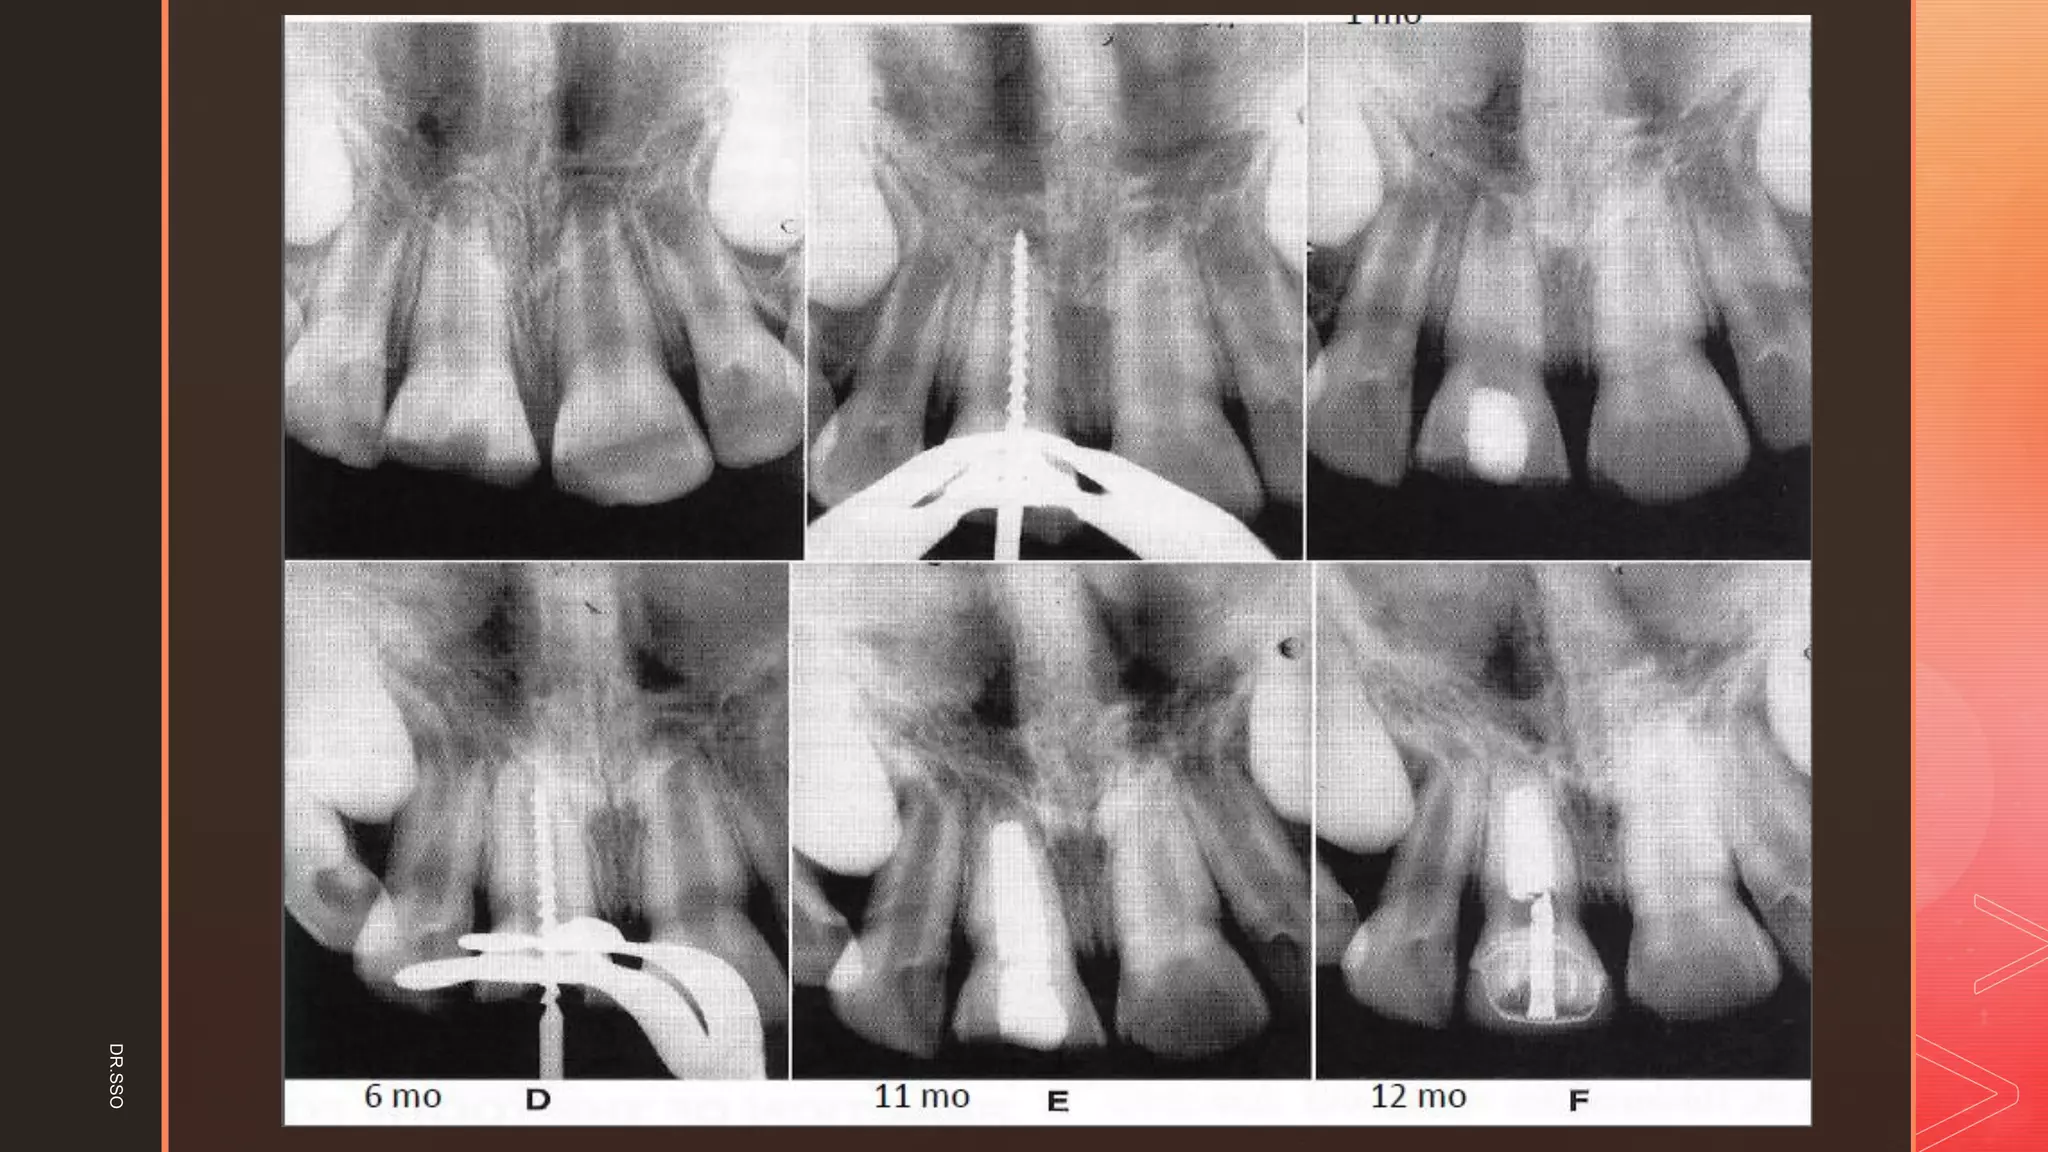

FOLLOW-UP

Time required

▪ 1 and 2 years depending on the degree of tooth development at the

time of the procedure.

Recalled every 3 months

▪ Clinically, the treatment was considered successful if there were

no signs or symptoms of pulp or periapical disease (no history

of pain and no clinical evidence of swelling or sinus tract).

▪ Radiographically, the treatment was considered successful if there

was continued growth of the root and canal narrowing, and no

widened periodontal ligament, no periapical radiolucency and

no internal or external root resorption.